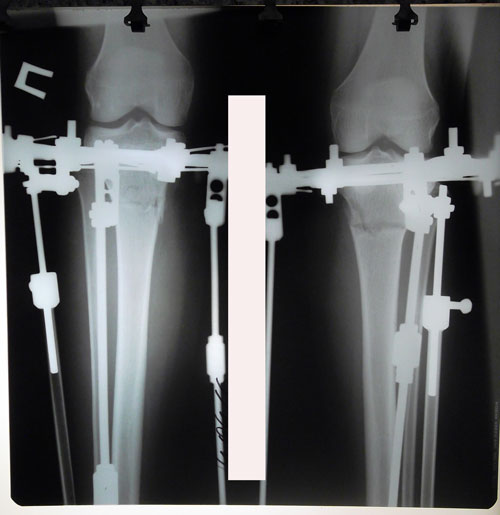

рентген перед фиксацией аппаратов.